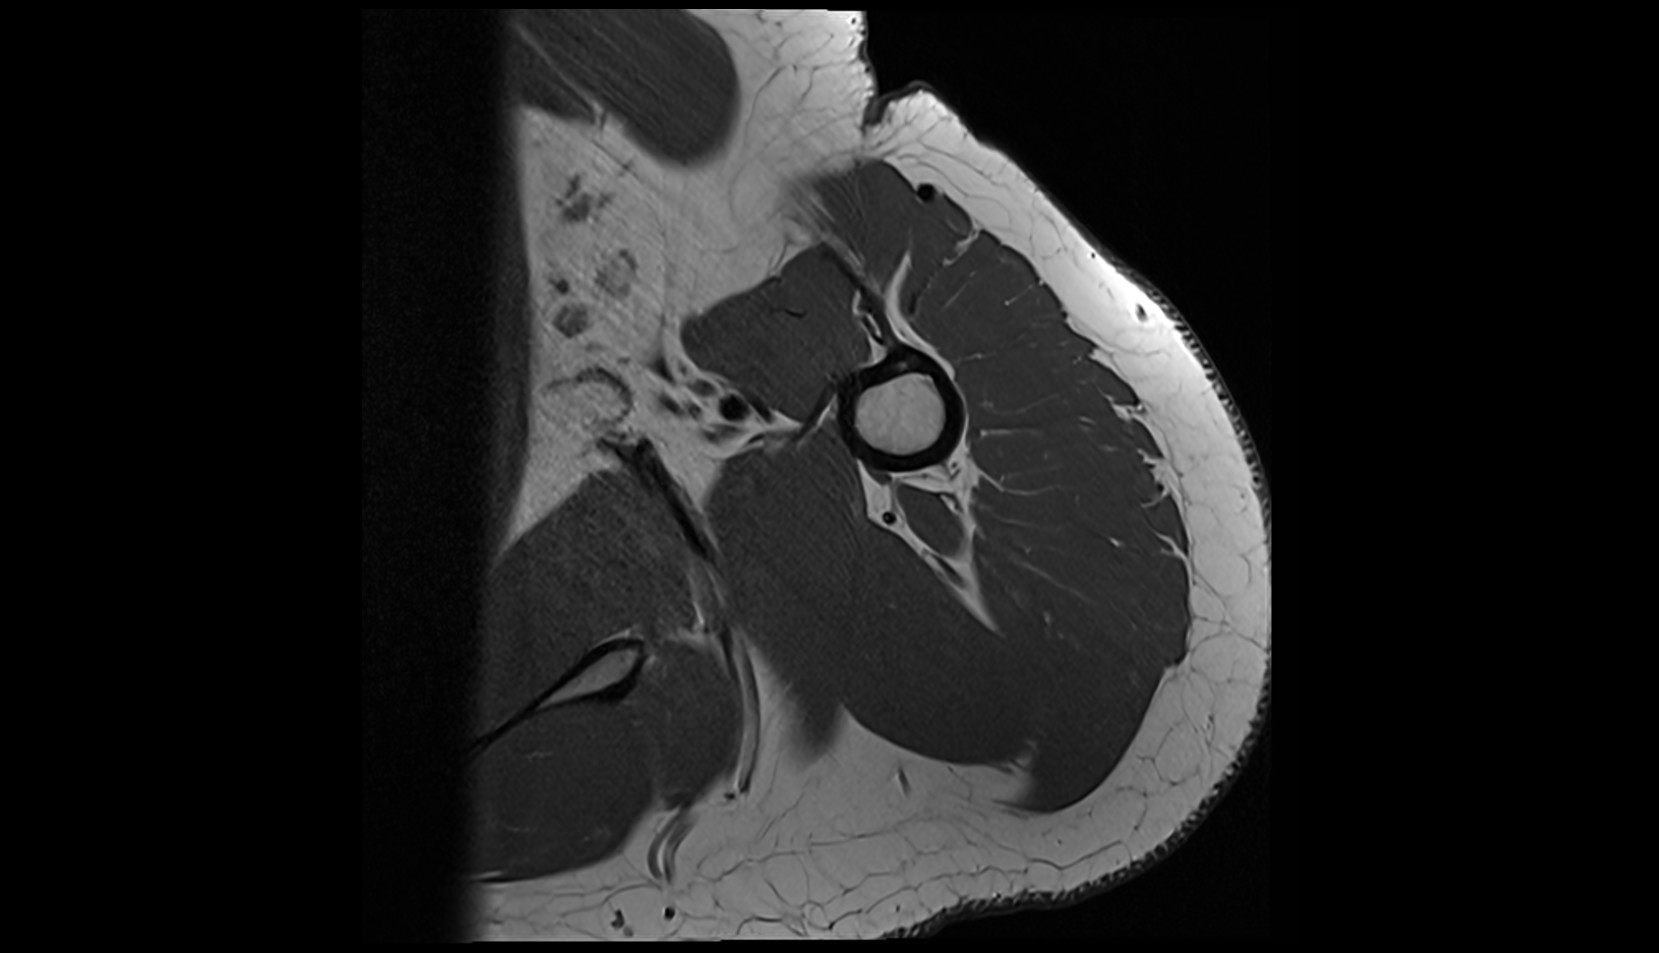

- Shoulder joint (glenohumeral joint)